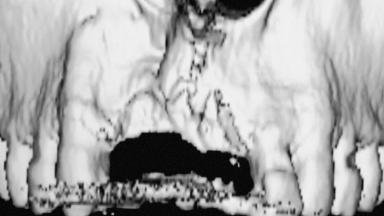

A 31-year-old man presented to our clinic 30 days after a motor vehicle accident in which he had suffered a dentoalveolar fracture in the anterior maxilla, including avulsion of teeth 12 and 11 and luxation of tooth 21. He was first treated on the night of the accident in a small city hospital with no oral and maxillofacial surgeon on the staff. A wired retention had been applied and the teeth repositioned to the best of the clinicians’ abilities. When he first presented to our care, the patient showed extrusion of teeth 12 and 11 associated with gingival recession due to bone loss in the anterior maxilla, and the stainless steel wires were still present.

Bone Augmentation Horizontal|Staged|Vertical

Bone Volume Deficient vertically or deficient vertically AND horizontally